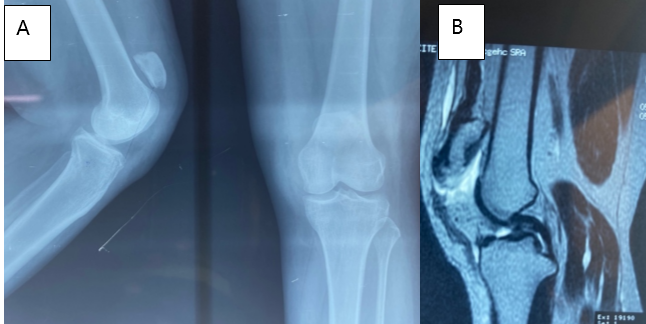

Mrs. , a 50-year-old woman with no significant medical history, presented 45 days after a closed injury of the left knee caused by a fall. Initial management had been performed in a non-specialized center. On examination, she walked with a limp. There was loss of active knee extension and a palpable defect along the patellar tendon, with intact skin. Standard radiographs revealed patella alta with a Caton-Deschamps index of 2 (Fig. 3). Magnetic resonance imaging (MRI) confirmed rupture of the patellar tendon (Fig. 3). Surgery was performed under spinal anesthesia with the patient supine. Intraoperative findings revealed a midsubstance rupture of the tendon. Tendon repair was performed and reinforced with a protective frame (Fig. 4). At 12-month follow-up, the patient had recovered active knee extension.

Figure 3: Standard radiograph (A) showing patella alta, and magnetic resonance imaging of the left knee (B) confirming patellar tendon rupture – Patient 2.